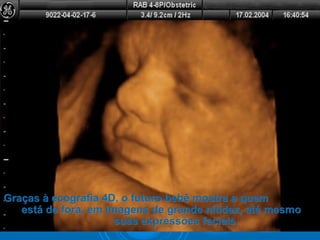

Graças à ecografia 4D, o futuro bebê mostra a quemGraças à ecografia 4D, o futuro bebê mostra a quem

está de fora, em imagens de grande nitidez, até mesmoestá de fora, em imagens de grande nitidez, até mesmo

suas expressões faciais.suas expressões faciais.